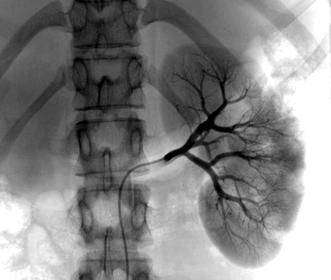

Renal Cell Carcinoma Normal Idiopathic, related to cigarette Can be caused by long term dialysis Develops from the renal tubules, destroying the kidney while it invades the blood vessels (IVC and renal vein), allowing spreading of malignant cells Symptoms: hematuria Common in males over 40 years old Radiographic Appearance: Angiography and ultrasound modality of choice, angiography: abnormal vascular ultrasound: composition of tumor along with invasion of renal vessels